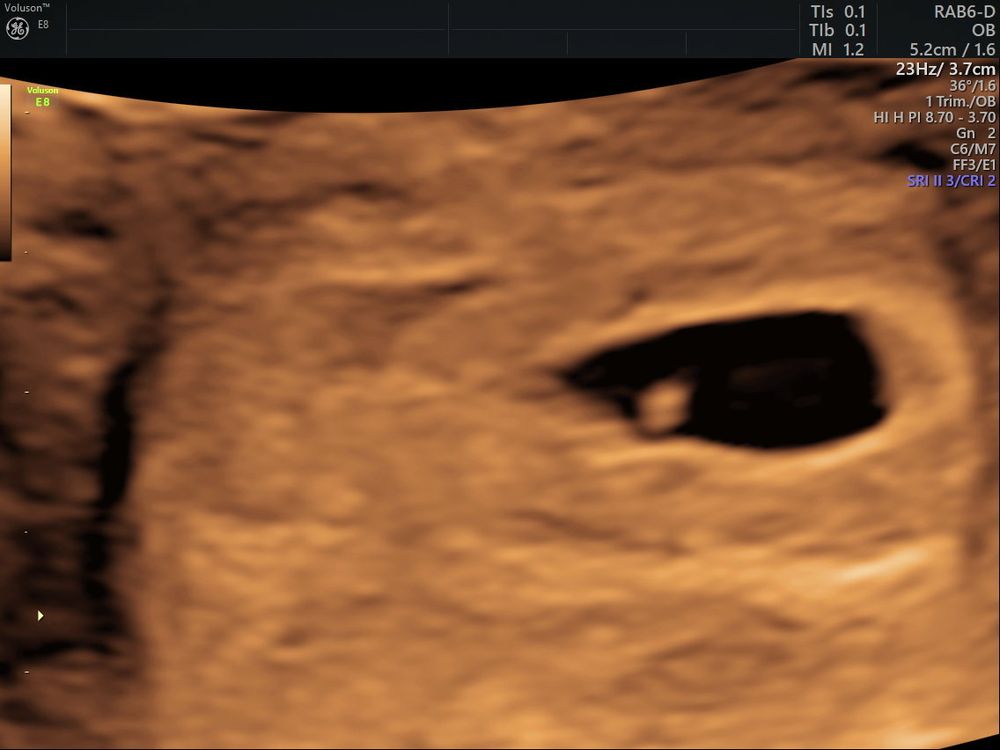

УЗИ 6+0. Увидели сб 🥹🥹🥹

Проверяют ВДПЯ, ктр и желточный мешочек. Эти данные должны быть в результате описаны. Сердечко это очень хорошо!